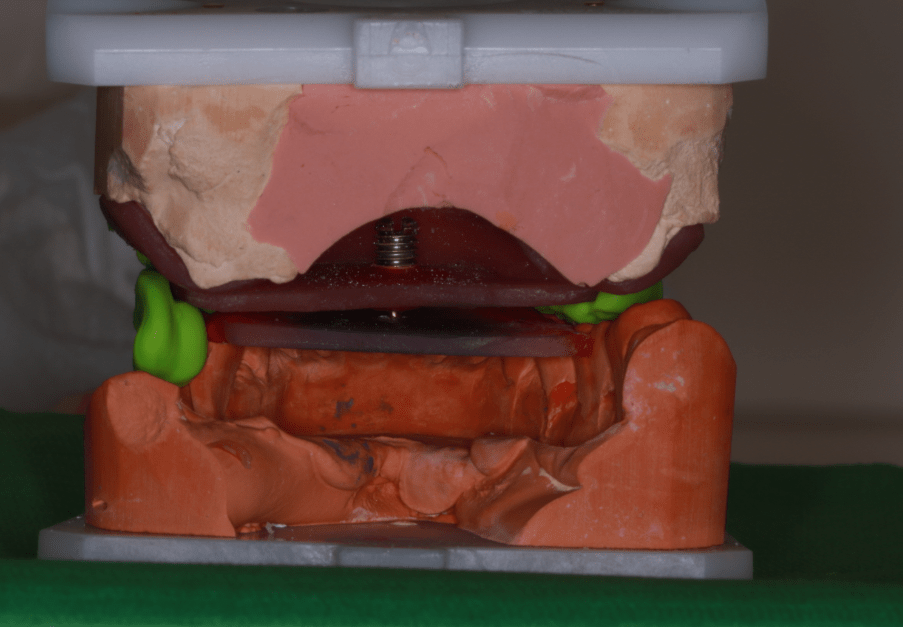

Majd ezt követően arcívvel meghatároztam a felső állcsont koponyához való elhelyezkedését, intraorális rajzolóeszközzel a felső és az alsó állcsont egymáshoz való viszonyát, majd az Arcus Digma készülékkel az individuális mozgáspályákat. Ez mind szükséges ahhoz, hogy egyedi, az egyén számára legkényelmesebb fogpótlás elkészülhessen, melytől jelen esetben páciensünk panaszainak rendeződését vártam.

Ezek segítségével a fogtechnikai laboratórium elkészített egy hosszú távú, ideiglenes pótlást, amelyet a páciens 3 hónapon át hordott, természetesen szoros nyomon követés, kontrollok mellett. Ennyi idő alatt a páciens panaszai nagyrészt meg is oldódtak.